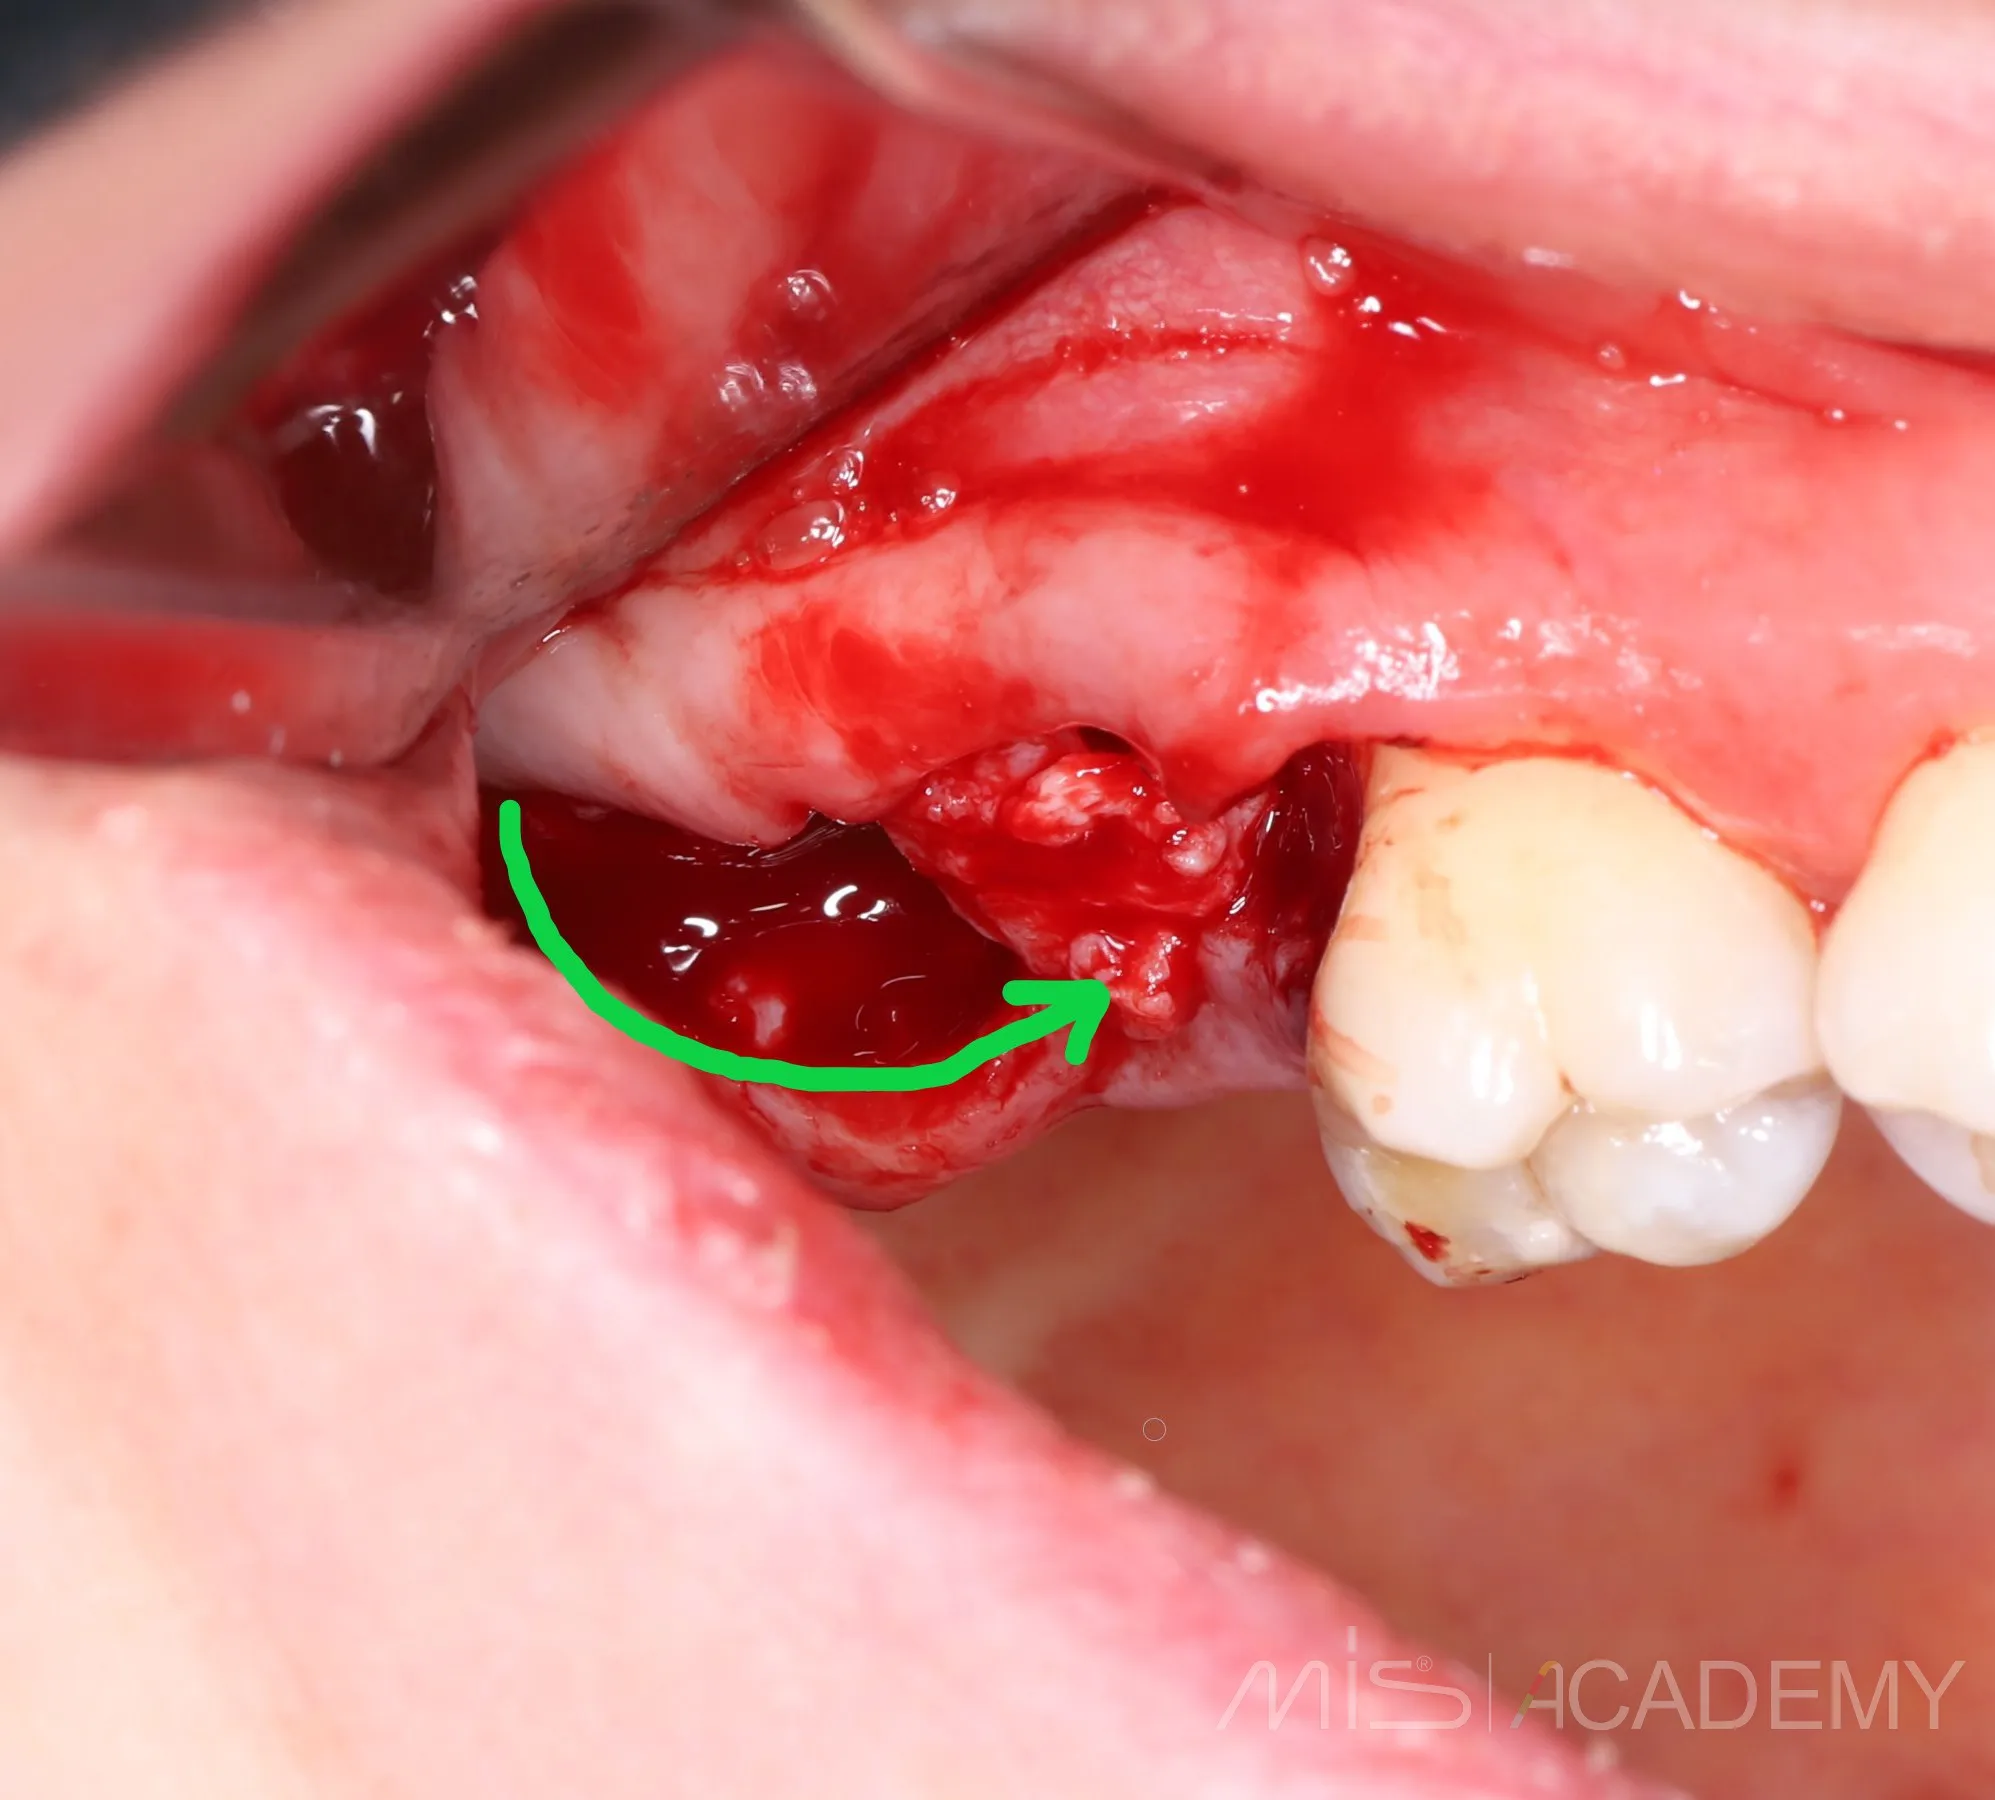

2 года назад закрыл соустье с пазухой в обл 17 зуба лоскутом с бугра «через себя»

Да, я подсмотрел это способ у Артура Политова. Сейчас пациентка пришла на плановый осмотр с другой проблемой,